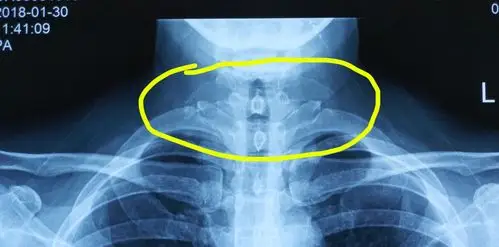

x线片:第7颈椎的双侧横突过长.